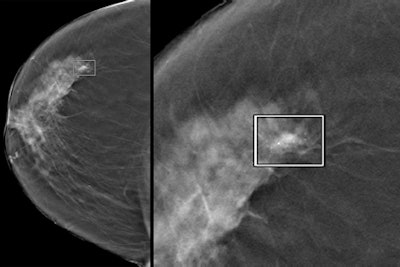

Left: A CAD-detected 12-mm invasive ductal carcinoma with associated microcalcifications. Right: A close-up of the tumor. Images courtesy of Dr. Giovanna Mariscotti from L'Azienda ospedaliero-universitaria San Giovanni Battista in Turin, Italy.High sensitivity, acceptable false positives